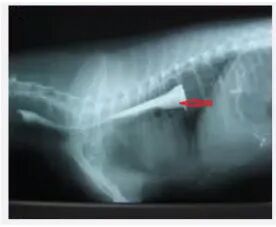

8.X线片如图所示,最可能的诊断是

A.肺肿瘤

B.大叶性肺炎

C.肺气肿

D.胸腔积液

E.异物性肺炎